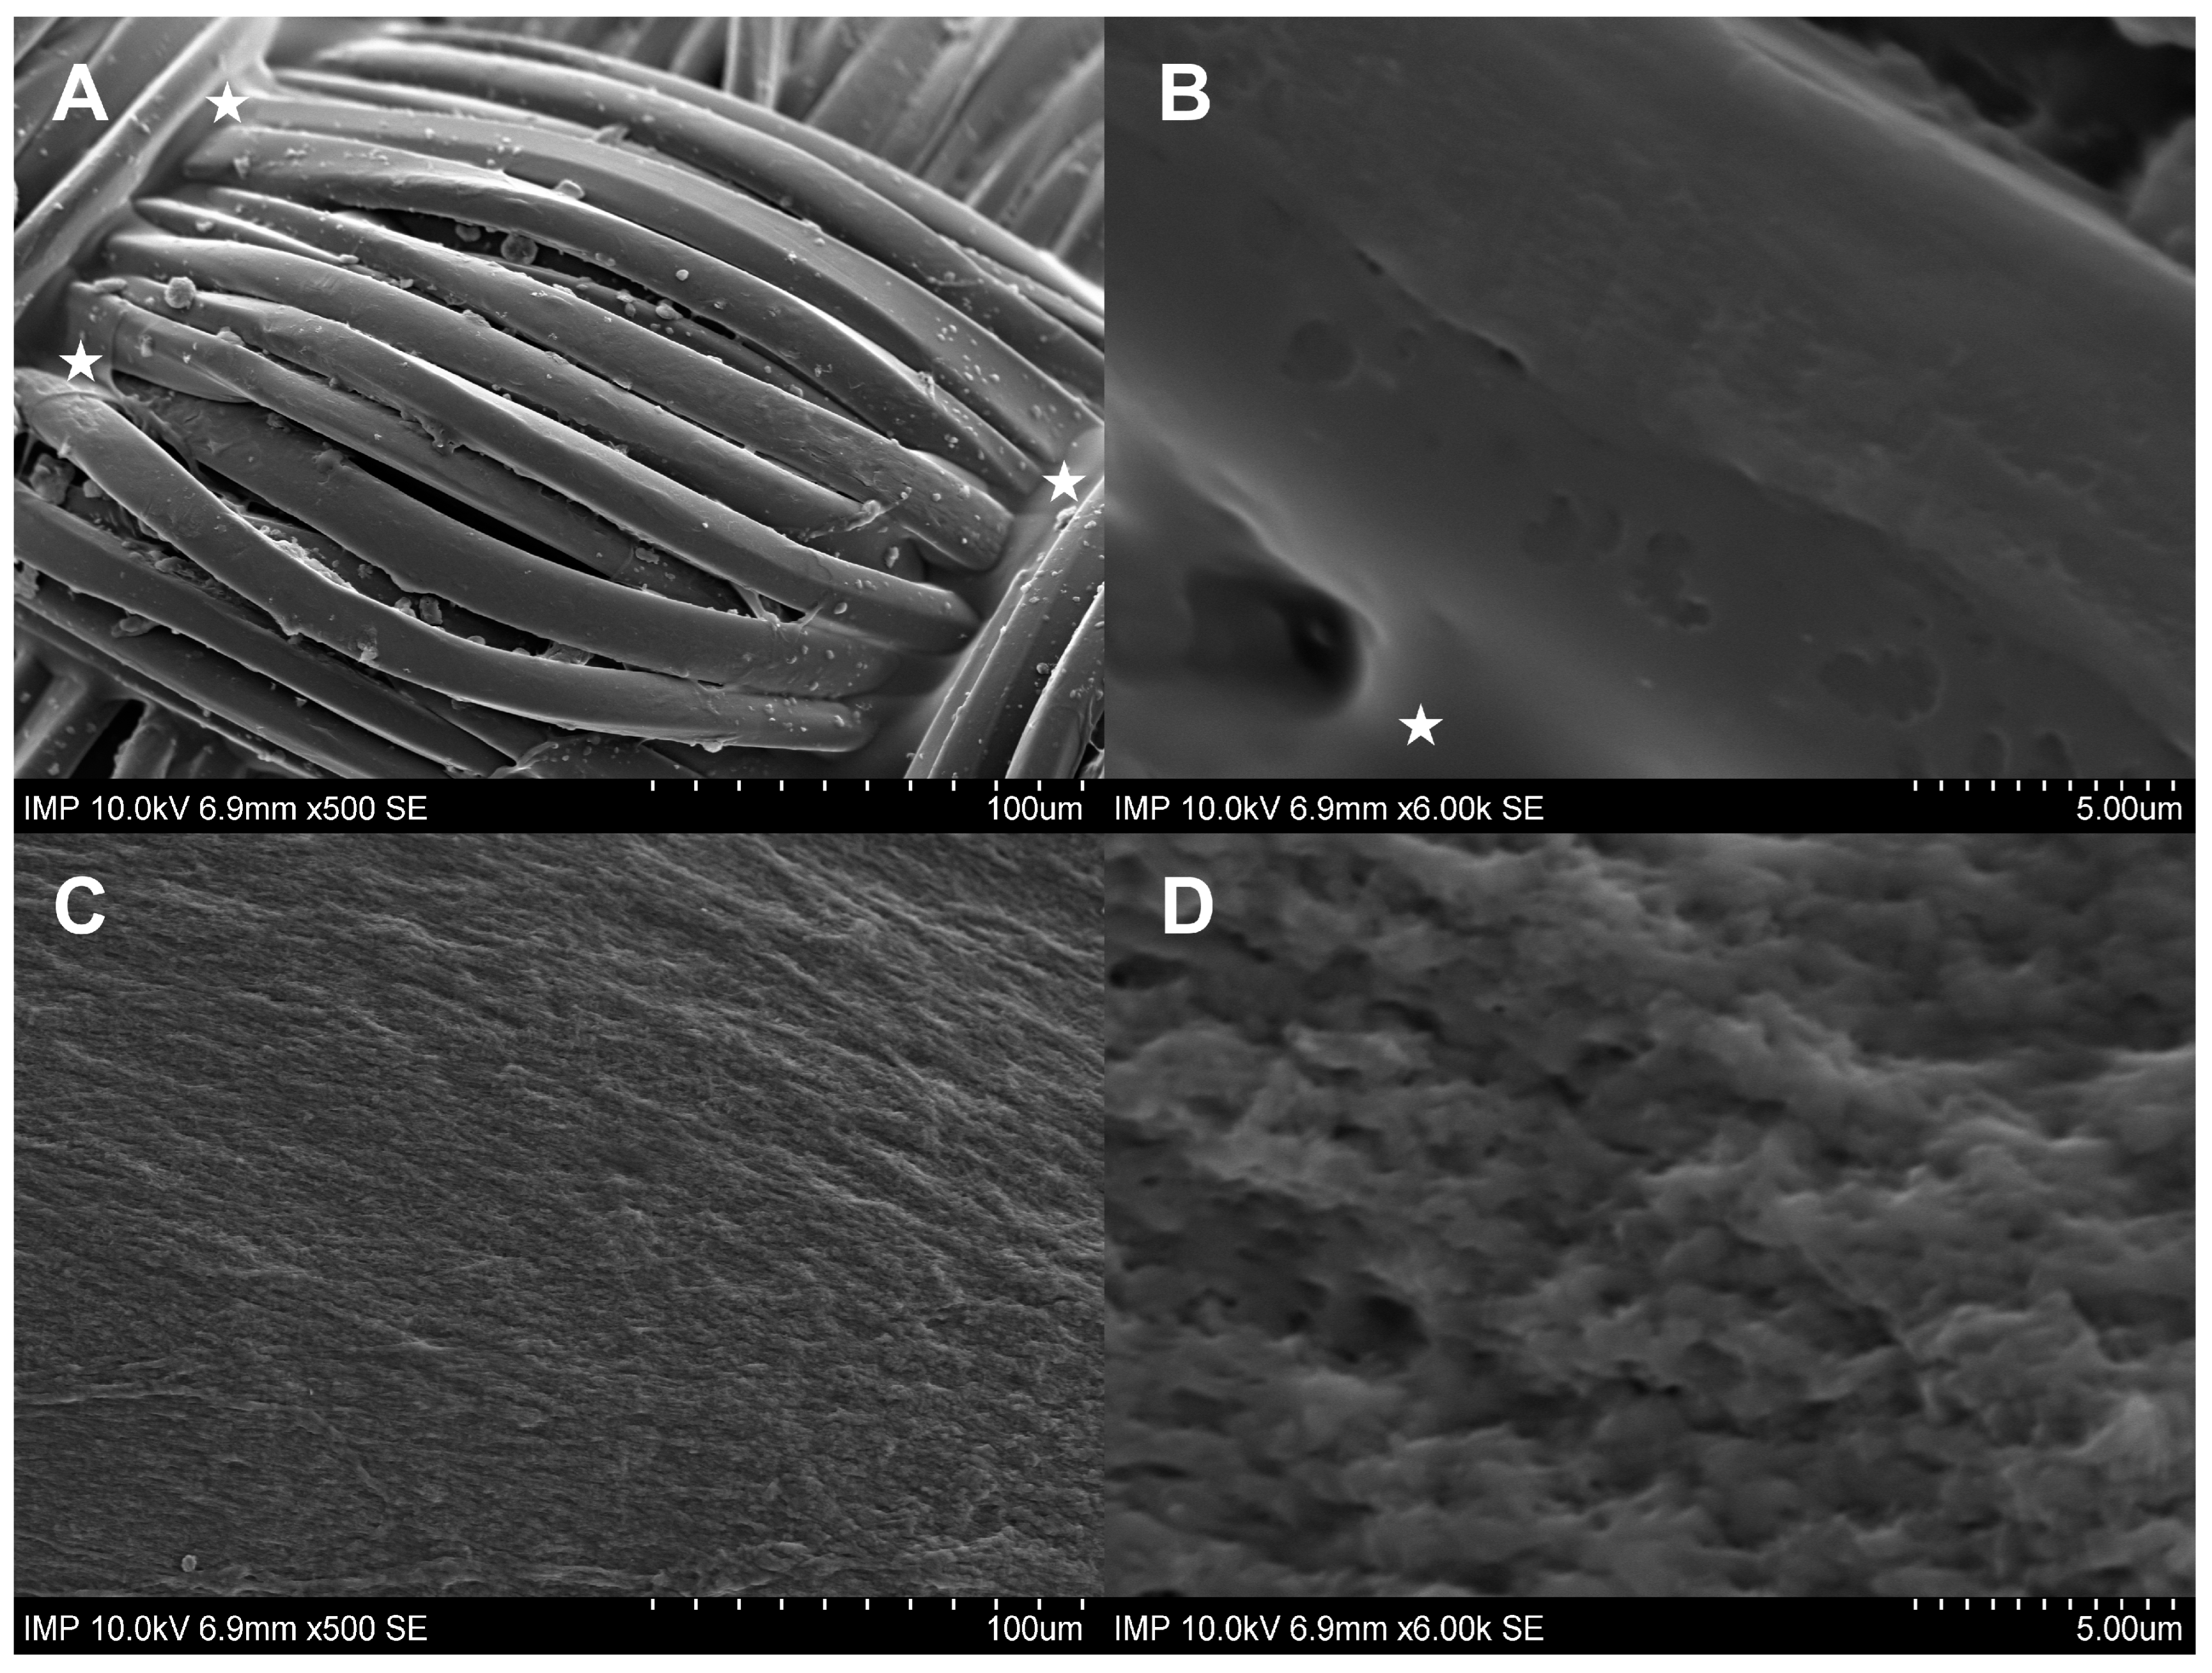

2.1. Surface Coating of the Grafts

4.2.5. Scanning Electron Microscopy